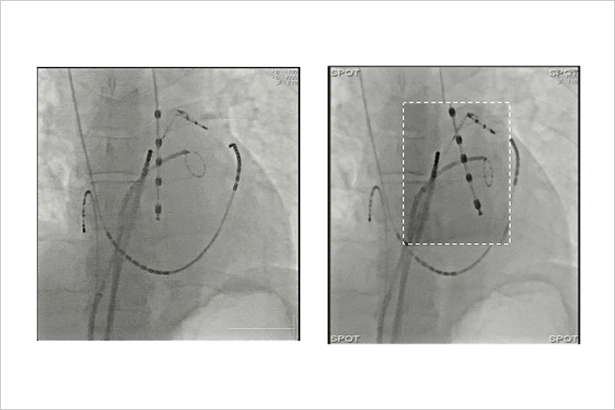

感興趣區域內顯示實時透視圖像,感興趣區之外無射線的靜止圖像作為背景,既保證了全局觀,又降低了輻射劑量